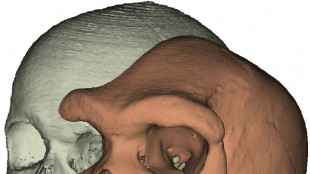

Pour comprendre l'évolution humaine, suivre la piste des sinus

Des paléoanthropologues ont réalisé la première étude d'envergure sur les sinus de la plupart des espèces humaines et grands primates, pour aider à comprendre l'évolution humaine, selon une étude parue vendredi.